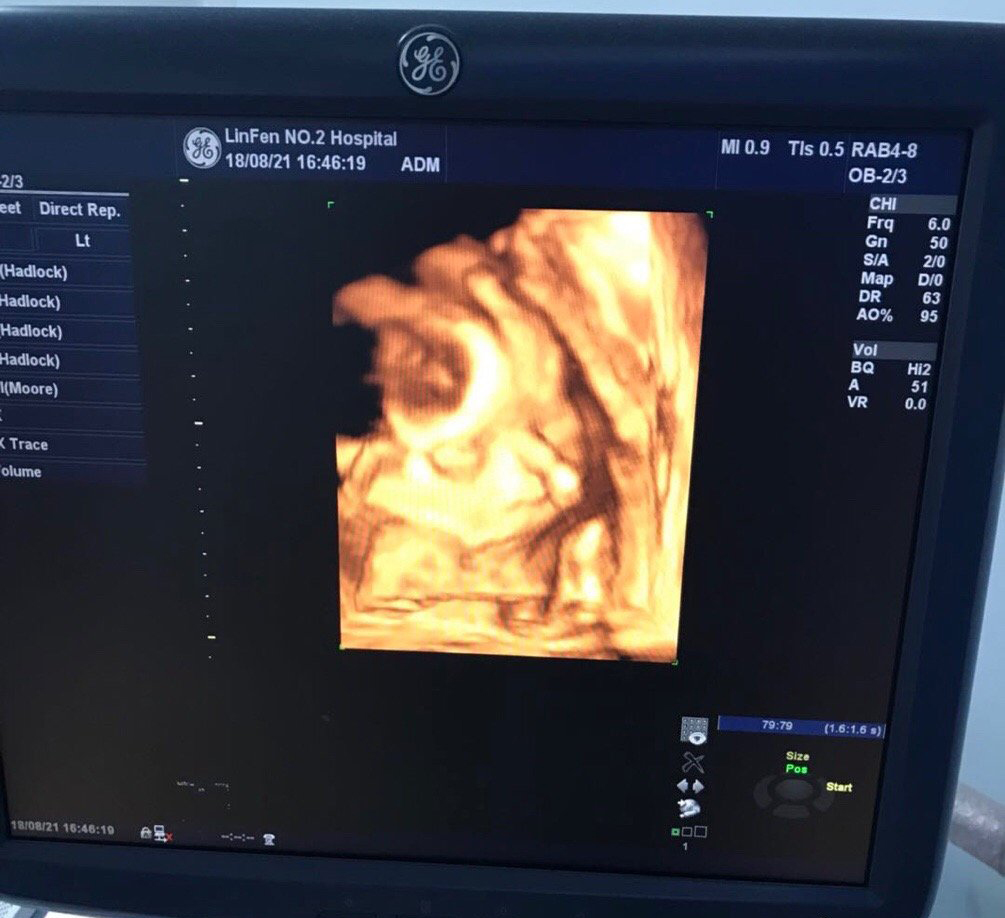

很快我的小外甥二毛一周岁了,参加完二毛的生日宴,下午和崔大一起去做了四维~之前就和我姐说我同事做四维宝宝位置不好总是趴着看不清楚,做了好几天才过… 没想到桃桃子也如此不给力,(又又一次被崔大批评我这个宝宝怎么这么事儿多)医生让吃个巧克力出去走走,和宝宝说说话让他赶紧转过来~走了二十分钟回去果然转过来了,医生说小嘴吧唧吧唧还在吞咽羊水,(忘了说,因为认识人 所以检查的时候偷偷告诉了我是个小棉袄~其实在做四维之前,就是情人节那天我特别想知道宝宝到底是我的小情人还是老羊的小情人,去老姑那里检查已经知道是老羊的小情人啦~)

总算是顺利通过了~